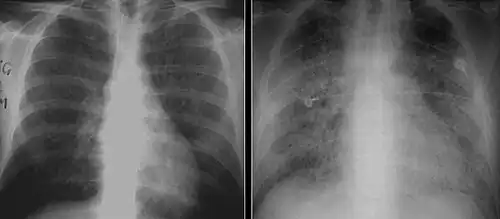

The diagnosis can be confirmed by the characteristic appearance of the chest X-ray and an arterial oxygen level (PaO2) that is strikingly lower than would be expected from symptoms. Gallium 67 scans are also useful in the diagnosis. They are abnormal in about 90% of cases and are often positive before the chest X-ray becomes abnormal. Chest X-ray typically shows widespread pulmonary infiltrates. CT scan may show pulmonary cysts (not to be confused with the cyst-forms of the pathogen).

Chest X-ray of increased opacification (whiteness) in the lower lungs. -

These chest radiographs are of two patients. Both show ground glass opacities. The left X-ray shows a much more subtle ground-glass appearance while the right X-ray shows a much more gross ground-glass appearance mimicking pulmonary edema.[7] -